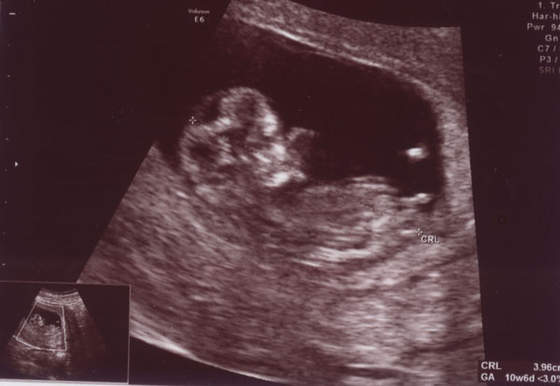

Mysza84 Takie maleństwo piekne, że nic tylko kochać..>>

GRATULUJĘ

świetne zdjęcie Mysza, gratuluję dzidziolka!

śliczna dzidzia drapie się po nosku! cudo!moja fasoleczka